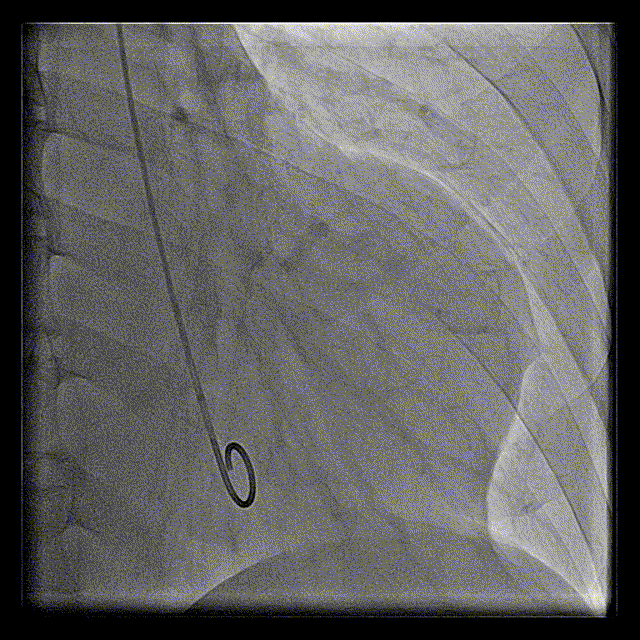

右冠脉造影

左冠脉造影

导丝微导管通过

交换导丝后造影

球囊扩张支架

IVUS证实在LAD真腔内,多次球囊扩张近中段闭塞处,但是前向血流始终无法恢复,提示左室壁室壁瘤形成后,无有效存活心肌。

IVUS证实在真腔

球囊再次扩张

微导管造影提示远端灌注不良

介入治疗最后造影

再次介入术后最后造影

左室造影

术中IVUS影像